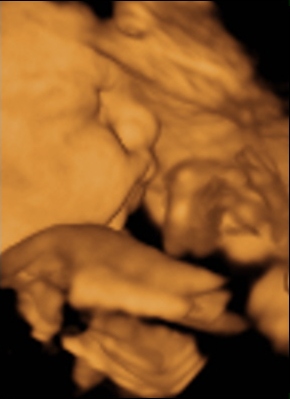

Ma tehát megjártuk a 4D-t meg a cipőboltot. 1,5 órát UHzott a csaj, mert Drága Kistesó nem akarta mutatni magát. Már tornáztam, ettem, ittam épp csak háztömböt nem mentem futni... A végén sikerült 1-2 jobb képet csinálni (azt is csak profilból). Súlya 2 kg (1900valamennyi), mindene 32 hetesnek megfelelő. Minden a helyén van és megvan, hosszú haja van és már most zsíros a Drágám.

No és képek: